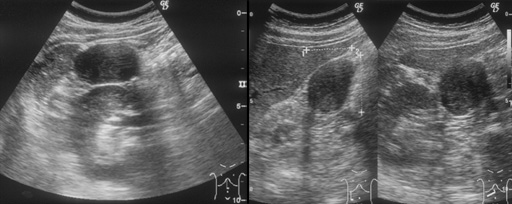

- 【超音波検査】

- 右腎腹側に3cm大の腫瘤を認める.内部は低エコーで比較的均一.ドプラでは辺縁を縁取る血管と流入する血管を認める.

図2 T2WI・DWI 図3

図3 図4 血管造影(腹腔動脈)